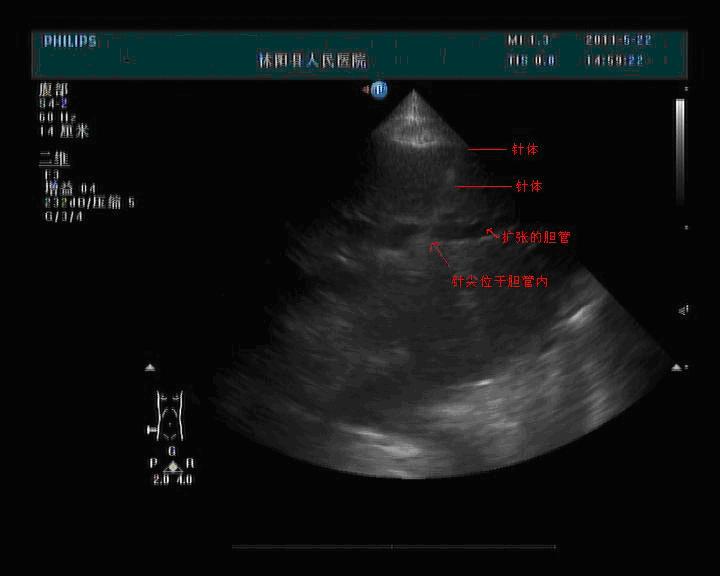

患者男性,62岁,胆囊癌术后,肝脏多发转移灶、阻塞性黄疸、肝门部胆管受压、肝内胆管重度扩张。普外科欲行经皮经肝胆管引流,来我功能检查科超声定位。

患者平卧位,常规超声检查、体表定位,消毒、铺巾、局麻、超声实时引导下进针,超声清晰的看到针体走行,当针尖到达胆管内后停止进针,导管连接的注射器内可见胆汁流出。此过程中患者无不适,超声检查胆管周围无血肿、积液等超声征象,遂结束超声引导。

图1:超声清晰显示针体及针尖方向,针尖位于胆管内。